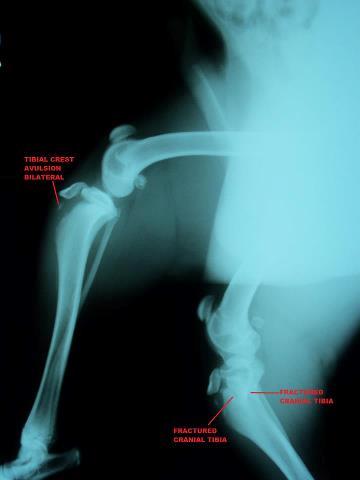

This x-ray says I have an Avulsion fracture. That's where a piece of boney tissue ( the tibia crest) has pulled away from the main bone by the action of a tendon.  Yeah it hurts a lot.

That's just the one leg, my other leg on the bottom has  fractures as well to the Tibia...  And to think I'm such a happy boy I've trying to run and play like this.